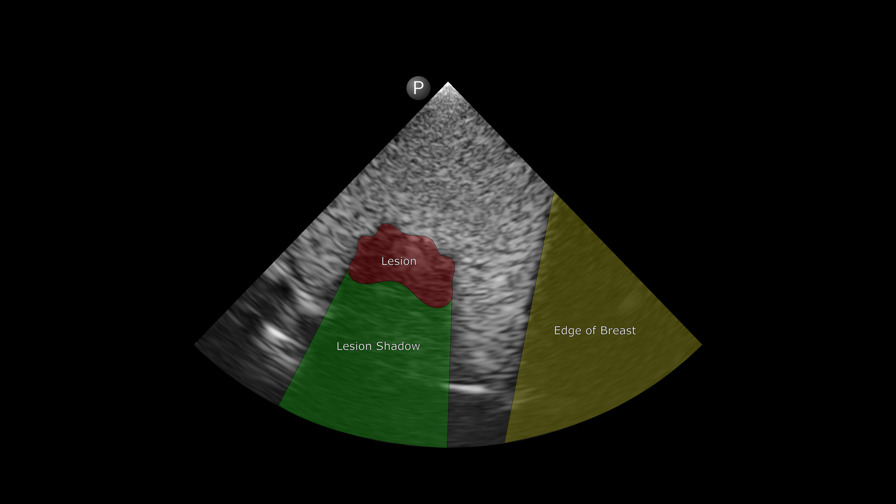

Breast lesion labeled

Using Digital Anatomy materials and a deidentified patient MRI scan, the research team wanted to create an ultra-realistic breast tissue model. From the GrabCAD software’s anatomical preset library, they chose Encapsulated Subcutaneous Fat to replicate the tissue of the breast itself and Solid Internal Organ 6 for the tumor.

With point of care ultrasound (POCUS), the team was able to visualize the lesion right away, but when they transitioned to the ultrasound suite with a more powerful transducer, they discovered that they needed to lower the frequency to match the POCUS settings. This adjustment ensured that the printed model would produce signals similar to those from actual human breast tissue.

“What seems to matter most is the difference between the object that you’re putting inside the material and the bulk material,” says Csordas. “Subcutaneous Fat and Solid Internal Organ 6 work well in contrast.”

“The two materials have a really nice echogenic interface,” adds Dr. Cox.

“We had to do a series of adjustments, but when we dropped the frequency to the same range as POCUS, the clinical unit began to show the lesion,” says Cox. “A low frequency setting is what allowed us to see the materials inside the model.”